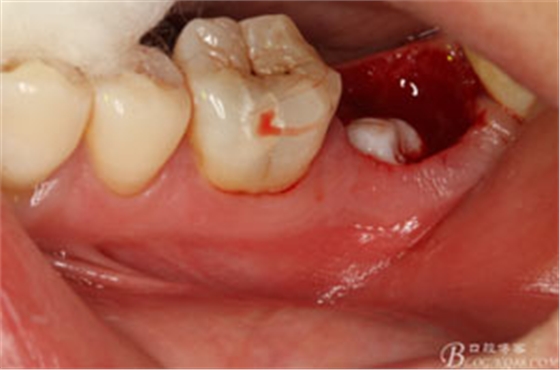

圖2.37牙冠基本完好,松動Ⅰ度。合面有一開髓孔被棉球覆蓋,頰側(cè)牙齦輕度紅腫。

圖3.取出棉球口內(nèi)發(fā)現(xiàn)37合面有開髓孔,探針出血,頰側(cè)牙齦紅腫